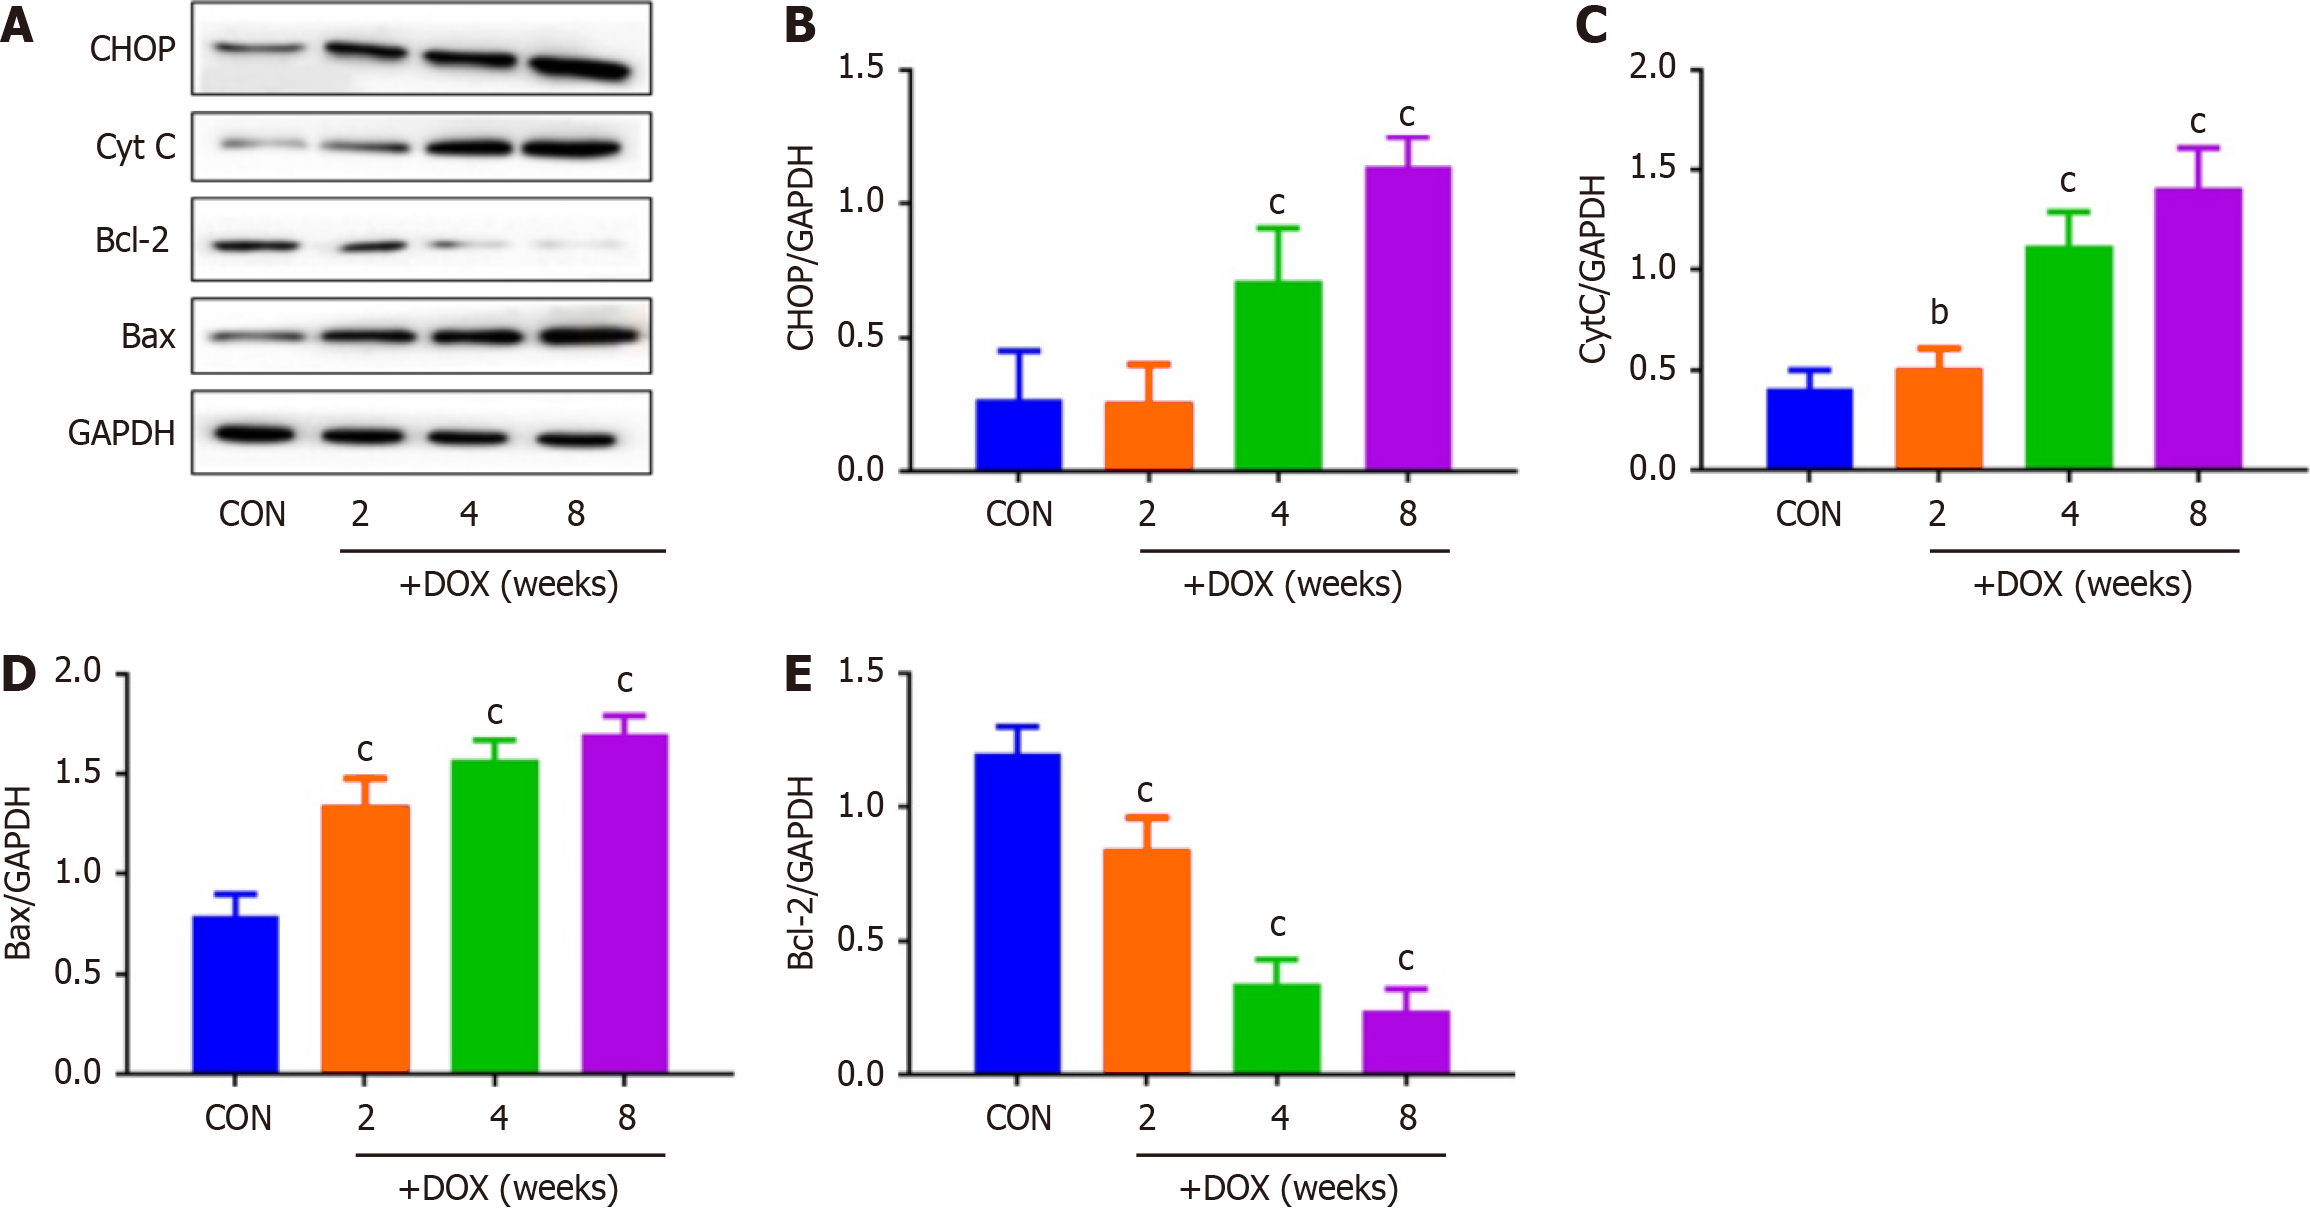

DOX reduced the expression of CALU in vivo in the DOX group, compared with the CON group (Figure 5). OPA-1 was decreased and DRP-1 was increased in the DOX group, compared with the CON group (Figure 6). To confirm the role of mitochondrial-induced apoptosis, we analyzed the expression of CytC, CHOP, Bax and Bcl-2. DOX increased expression of CytC, CHOP and Bax and reduced expression of Bcl-2 in the DOX group (Figure 7).

It has been reported[22] that CALU plays an important role in the occurrence and development of acute myocardial ischemia, arrhythmia and other diseases. Our results also showed that expression of CALU was significantly decreased in the DOX group compared with the CON group. This indicated that expression of CALU was decreased by DOX. We found that DOX decreased rat body weight, and increased the heart weight–body weight ratio. DOX reduced expression of CALU due to Ca2+ overload, and increased apoptosis of myocardial cells. In vivo experiments showed that DOX reduced expression of CALU, OPA-1 and Bcl-2, and increased expression of DRP-1, CytC, CHOP and Bax in rats.